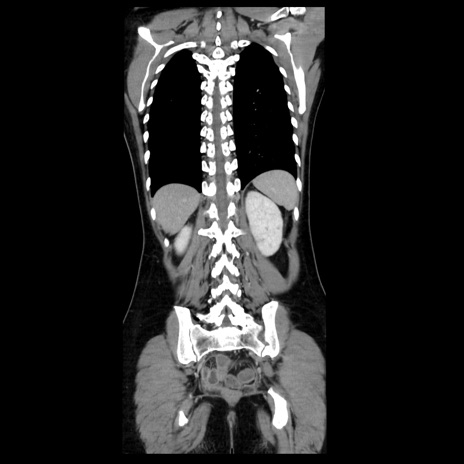

症例39(冠状断像)

【症例】40歳代女性

【主訴】上下腹部痛

【現病歴】2日目から下腹部痛あり。夜間は痛みで眠れなかった。昨日より上腹部痛と下痢が出現。臥位で痛みは軽快したため、休んでいた。本日になって臥位でも立位でも痛みが強くなってきたため救急要請。

【既往歴】子宮内膜症

【身体所見】部:平坦・軟、左上下腹部に圧痛あり、反跳痛あり。

【データ】WBC 21800、CRP 26.78

CT